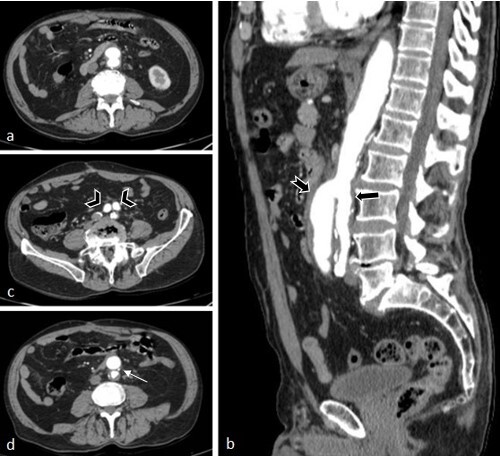

Persistent double dorsal aorta is an extremely rare congenital anomaly, with only 13 cases published to date. The objective of this study is to present this embryological variant as observed in the abdominal aorta of a patient. The anatomical description was written up on the basis of a review of electronic medical records and imaging exams. The patient in this case was an elderly 79-year-old man who presented at emergency with pain at rest in the left lower limb. He was admitted and laboratory tests and imaging exams were ordered. The variation was an imaging finding observed on angiotomography, consisting of complete separation of the abdominal aorta into two portions - a ventral and a dorsal, with different calibers - at the level of the third lumbar vertebra. There was also an anomalous origin of the inferior mesenteric artery.